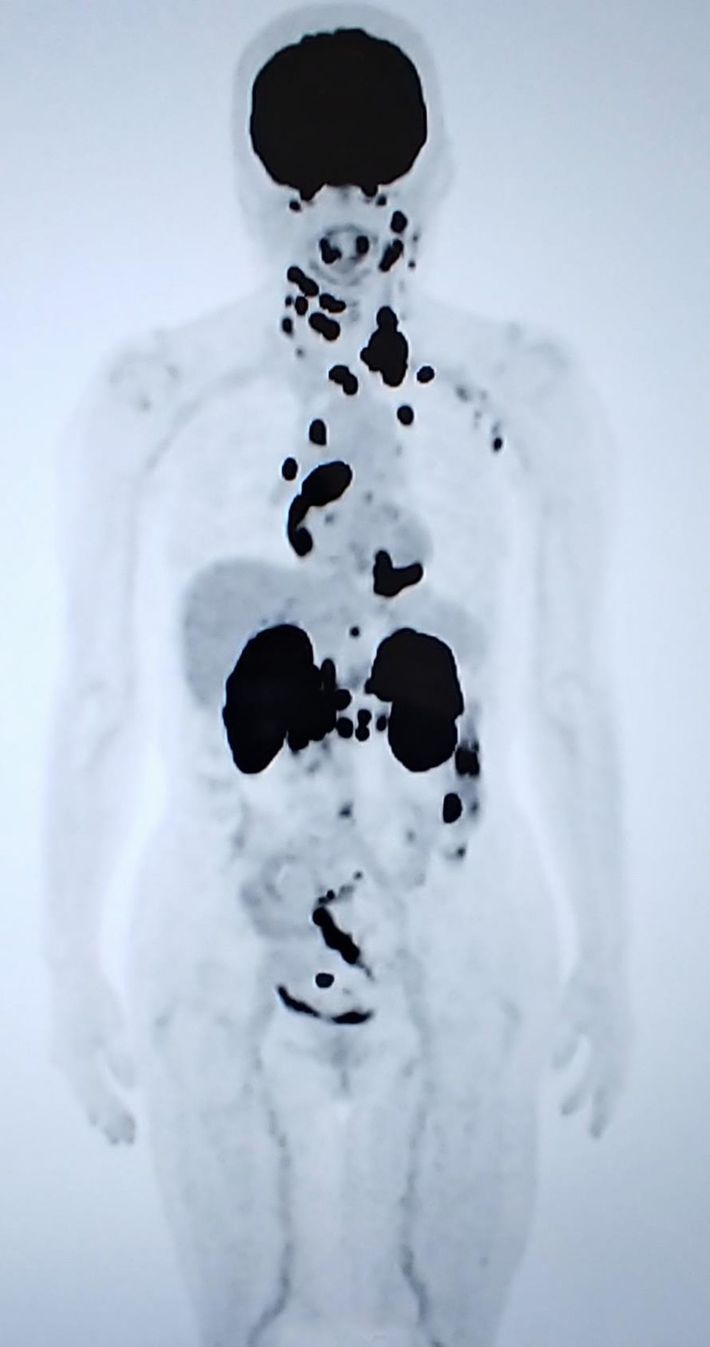

PET-CT検査の画像(全身)